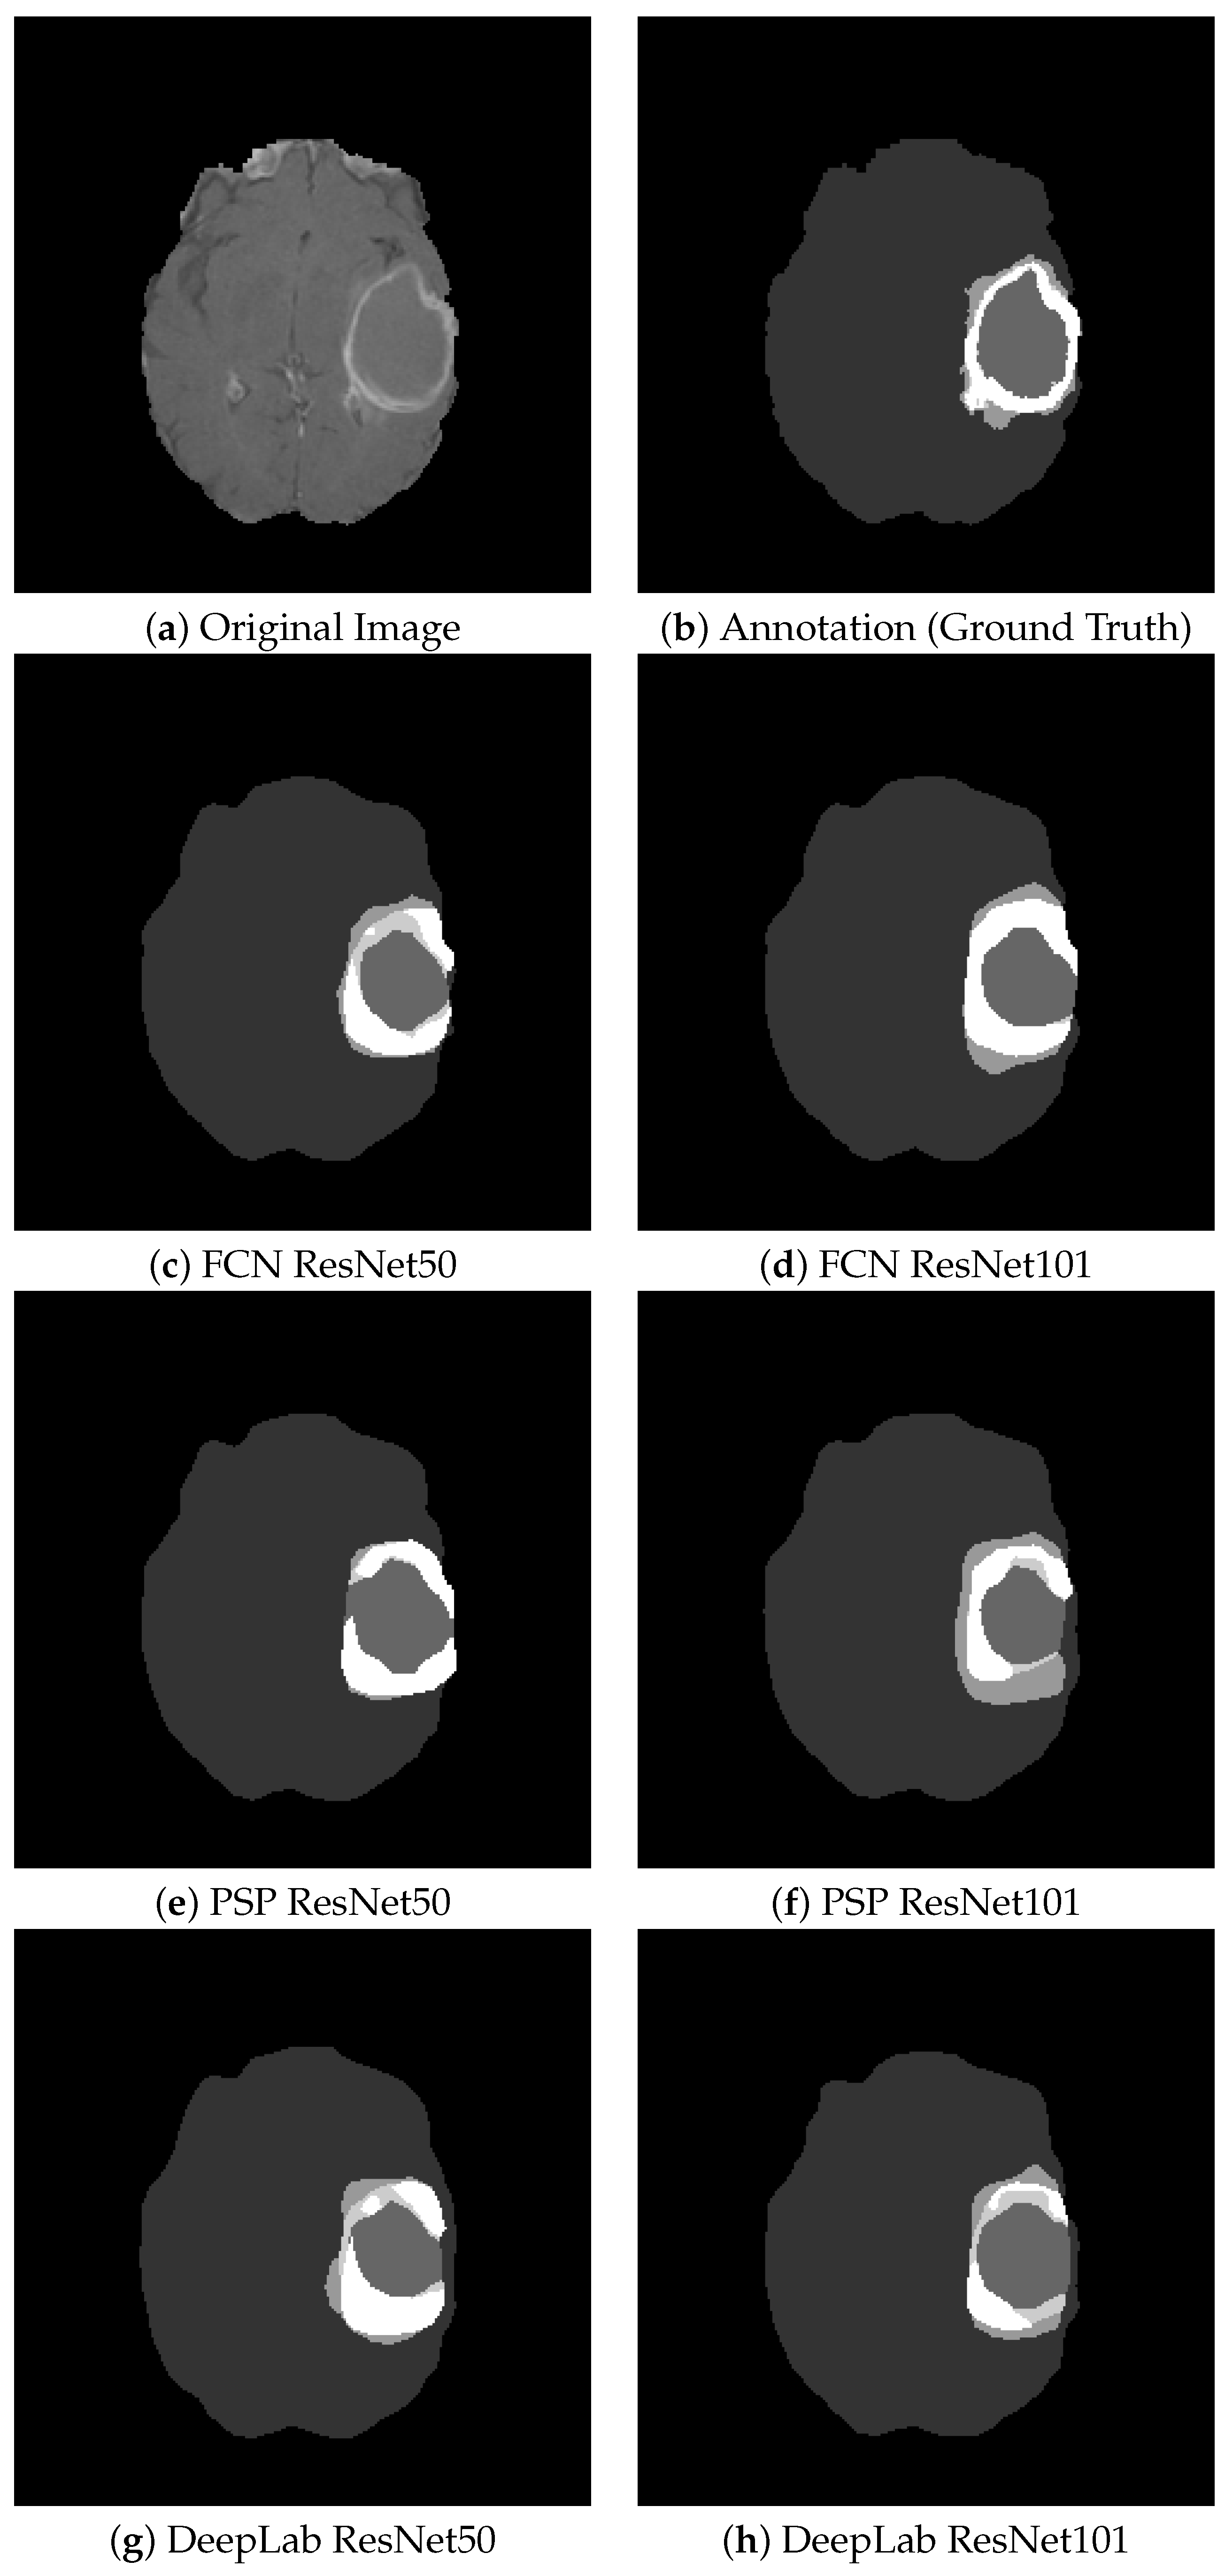

Figure 10 shows some segmentation results for the visual comparison of different tumor types and the six architectures studied. On average, this barely visible difference is around 1–2%. There is no quantitative evidence clearly showing that one architecture is better than all the others. In different images, the other architecture outstrips the rest. This led to the idea of combining them into an ensemble model.

Figure 10. Segmentation Results of the 6 Architectures: visually, the segmentations are similar, and the difference on average for the whole dataset is about 1–3%.